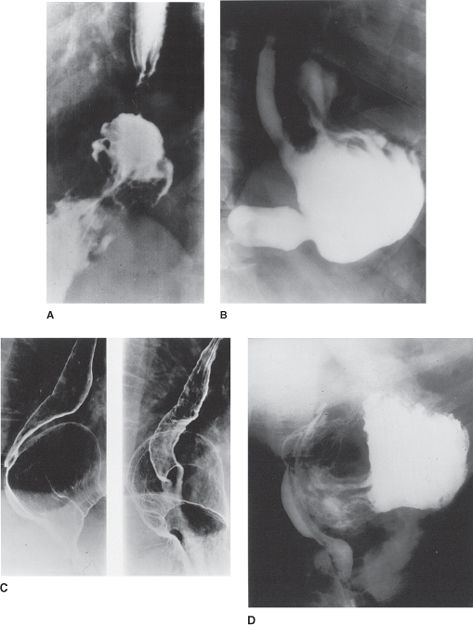

21. A patient with dysphagia undergoes a barium swallow. Based on the image in Fig. 25-12, the most likely diagnosis is

Answer: B

(See Schwartz 9th ed., p 852, and Fig. 25-12.)

FIG. 25-12. Barium esophagogram of patient with diffuse spasm showing the corkscrew deformity.